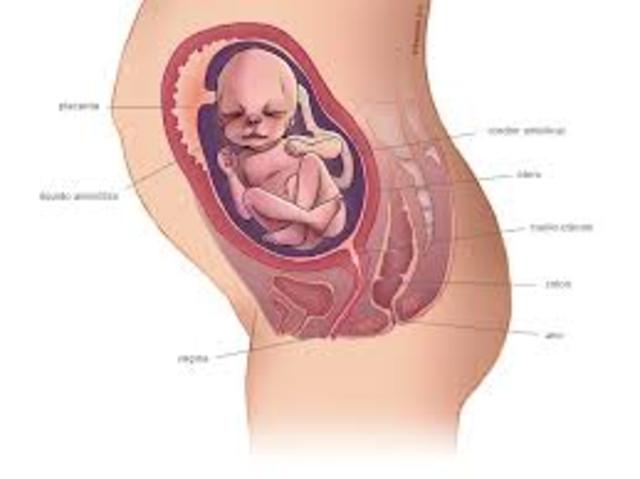

• Semana 38-40

Semana 38-40

El lanugo ha desaparecido excepto en la parte superior de los brazos y los hombros.

Las uñas pueden extenderse más allá de las puntas de los dedos.

Se presentan pequeños brotes mamarios en ambos sexos.

El cabello de la cabeza ahora es grueso y más denso.